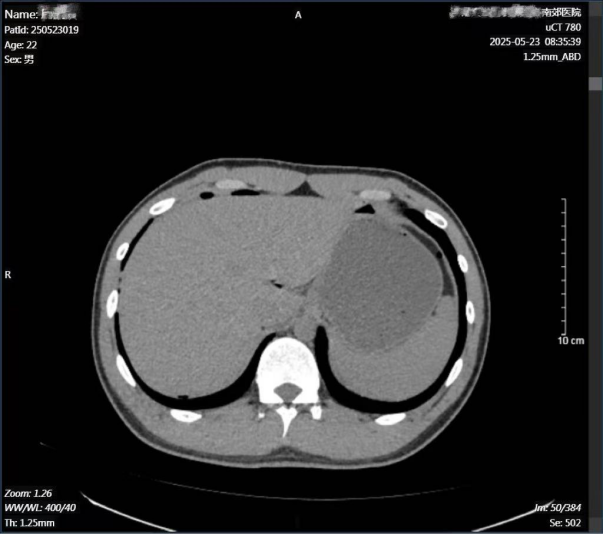

23号凌晨,一场车祸中的重伤者送到了济南南郊医院。伤者是一名22岁的小伙子,因为多发伤,被送到南郊医院的神经外科,腹部CT检查未见外伤改变。在神经外科初步处理了脑震荡、头皮裂伤、腰椎骨折、左膝部挫裂伤和左股外侧肌腱膜破裂等外伤后,伤者在几小时后突发剧烈的腹部疼痛,随即被转至普外科进行紧急处理。

经普外科会诊,再次CT检查考虑是空腔脏器破裂导致的严重腹膜炎,查血常规白细胞为29.98×10^9/L。普外科王兆太主任团队为其制定了详细的手术方案,并为可能出现的突发状况制定了预案。在麻醉科、手术室等科室的通力合作下,为伤者进行了腹腔镜手术。